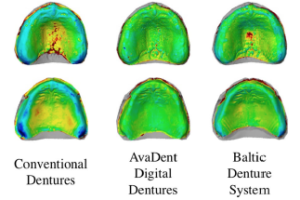

CAD/CAM PRODUCES DENTURES WITH IMPROVED FIT

Otto Steinmassl1 & Herbert Dumfahrt2 & Ingrid Grunert2 & Patricia-Anca Steinmassl2. Objectives Resin polymerisation shrinkage reduces the congruence of the denture base with denture-bearing tissues and thereby decreases the retention of conventionally fabricated dentures.

CAD/CAM MILLED REMOVABLE COMPLETE DENTURES: AN IN VITRO EVALUATION OF TRUENESS

Murali Srinivasan1 & Yoann Cantin1 & Albert Mehl 2 & Harald Gjengedal3 & Frauke Müller1,4 & Martin Schimmel1,5. Objectives This study aimed to compare the trueness of one type of CAD/CAM milled complete removable dental prostheses (CRDPs) with injection-molding and conventionally manufactured CRDPs.